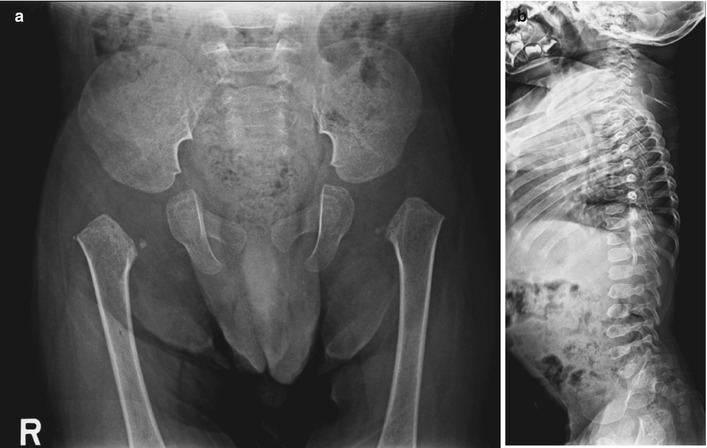

- Компьютерная и магнитно-резонансная томография (КТ и МРТ). Эти методы помогают выявить аномалии в структуре костей. Часто обнаруживаются клиновидные деформации грудных и поясничных позвонков, а также уменьшение толщины и высоты межпозвоночных дисков. Эпифизы некоторых костей могут утолщаться и деформироваться, также наблюдаются изменения в строении коленных суставов и головки бедра.

Спондилоэпифизарная дисплазия – генетически гетерогенное наследственное заболевание из группы остеохондропатий, характеризующееся пороками развития позвонков, эпифизов длинных трубчатых костей и суставов.